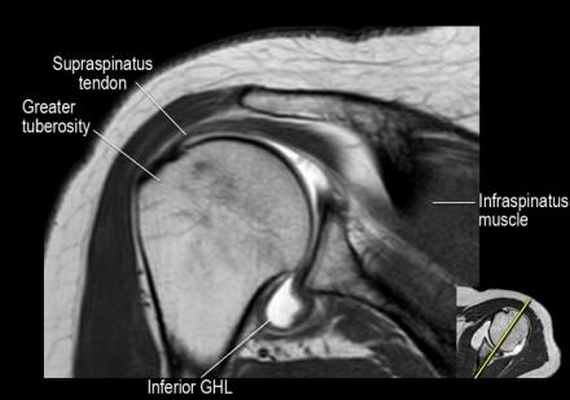

Изображение задних отделов плечевого сустава.

Отображены надостная, подостная и малая круглая мышцы и их сухожилия. Все они прикрепляются к большому бугорку плечевой кости. Сухожилия и мышцы манжеты вращателей участвуют в стабилизации плечевого сустава во время движения. Без манжеты вращателей головка плечевой кости частично сместилась бы из суставной впадины, уменьшив силу отведения дельтовидной мышцы (мышцы вращательной манжеты координирует усилия дельтовидной мышцы). Повреждение манжеты вращателей может привести к смещению головки плечевой кости кверху, в результате вызвая высокое стояние головки плечевой кости.